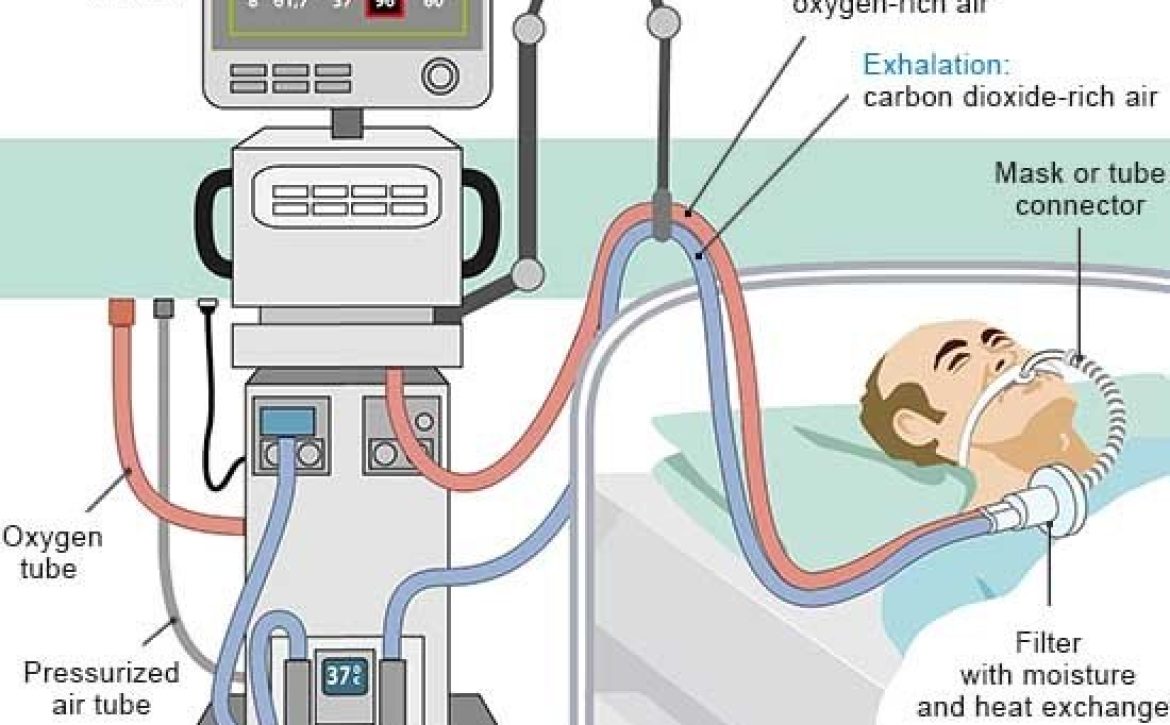

تبدیل یک اتاق معمولی به واحد مراقبت ویژه کار سادهای نیست. چالش اصلی در انتقال بیمار از ICU به منزل، فراهم کردن تخت برقی، اکسیژنساز، ونتیلاتور و سیستم برق اضطراری (UPS) است. اتاق باید دارای تهویه عالی و دسترسی سریع برای تیمهای درمانی باشد.

پزشکان معمولاً زمانی با انتقال بیمار از ICU به منزل موافقت میکنند که وضعیت بیمار به «پایداری نسبی» رسیده باشد. بیمارانی که نیاز به دیالیز مداوم یا جراحیهای پیاپی ندارند اما همچنان به دستگاه تنفس مصنوعی (ونتیلاتور) یا تغذیه لولهای وابستهاند، بهترین کاندیداها برای این طرح هستند.

* آیا پرستار انتخاب شده تجربه کار با ونتیلاتور و دستگاه ساکشن را دارد؟

* آیا منبع ذخیره اکسیژن برای حداقل ۲۴ ساعت (در صورت قطع برق) موجود است؟